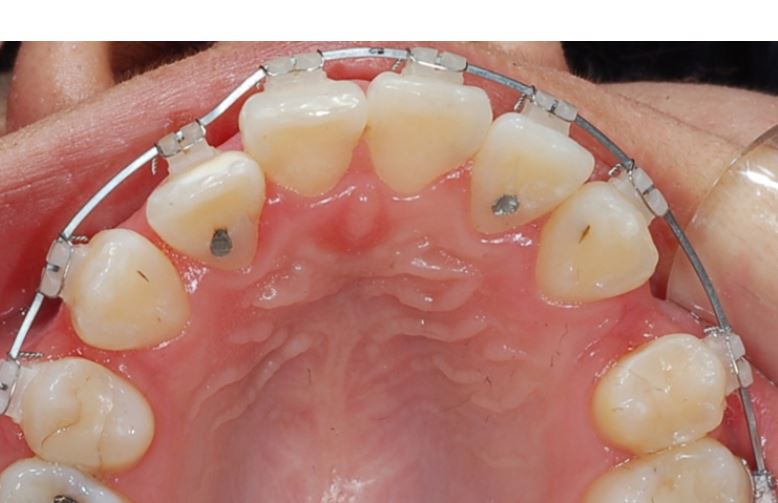

실제 치아 사진과 교정 시뮬레이션을 이용한 결과 예측 사진

특히 교정 스크류를 사용하여

뒤로 당기는 경우

브라켓과 치아 사이에

적절한 마찰이 잘 결리기

때문에 치아들이 서로 틀어지지 않고

방향을 유지하면서

빈 공간으로 이동을 잘 합니다.

발치한 자리로 앞니가

가지런하게 잘 이동한 뒤 모습입니다.